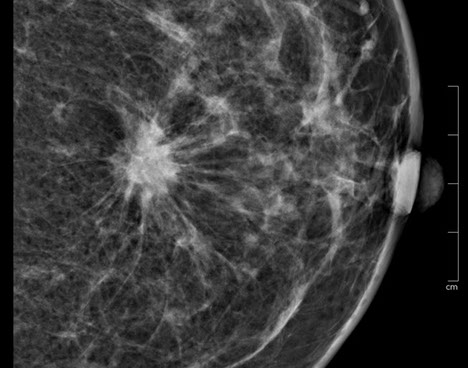

3.  Exaktere Bildanalyse – sicherere Diagnose

Durch die höhere Kontrastauflösung bei einem höheren Kontrast-Rausch-Verhältnis wird die Erkennungsrate von malignitätsverdächtigen Veränderungen deutlich verbessert. Der Radiologe kann auf hochauflösenden 5 MP-Monitoren die Dichte, Form und Kontur von Gewebearealen wesentlich exakter differenzieren und so gutartige von bösartigen Herdbefunden sicherer unterscheiden. Im Speziellen sind Mikroverkalkungen auch bei der dichten Brust besser zu analysieren.

40 % der Mammakarzinome weisen Mikroverkalkungen auf. Mikrokalzifikationen sind auch bei sehr dichtem Brustgewebe immer sichtbar. Eine Mammographie sollte daher ab dem 40. Lebensjahr die primäre Untersuchungsmethode sein.